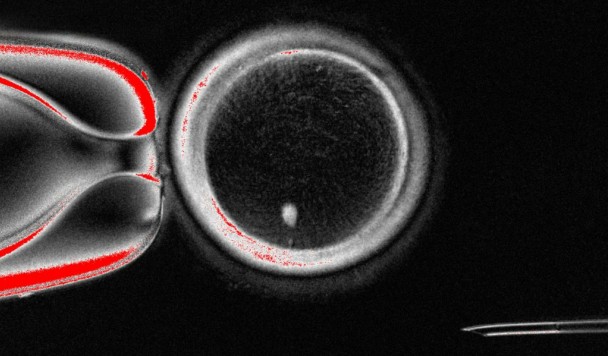

Метод основан не на перепрограммировании стволовых клеток, а на технике переноса соматического ядра. Исследователи внедряли ядро кожной клетки в донорскую яйцеклетку, из которой было удалено собственное ядро. Цитоплазма донорской клетки запускала процесс отбрасывания половины хромосом, имитируя естественный мейоз.

Таким образом формировалась гаплоидная яйцеклетка, которую можно было оплодотворить сперматозоидом стандартным методом ЭКО. Полученные эмбрионы содержали равный набор генов от обоих родителей.

В ходе эксперимента учёным удалось получить 82 функциональные яйцеклетки и оплодотворить их сперматозоидами. Большинство остановилось на стадии деления в 4–8 клеток из-за хромосомных нарушений. Однако около 9% эмбрионов развились до стадии бластоцисты на шестой день.